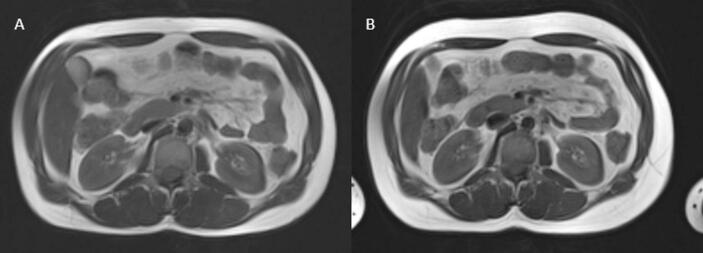

Conducted at the Medical University of Vienna between 2019 and 2022, the study included 15 TW and 20 TM. We conducted magnetic resonance imaging and spectroscopy to determine the visceral (VAT) and subcutaneous adipose tissue (SAT) amounts, the VAT/SAT ratio, and the intraorgan lipid content (liver, pancreas, myocardium), bloodwork, and an oral glucose tolerance test at baseline and after 6 months of GAHT.

Abstract Image